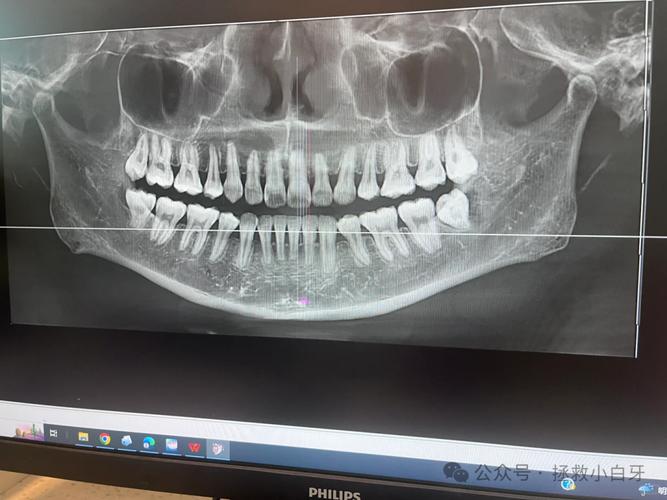

牙齿矫正是一个系统性工程,需要医生全面评估口腔状况、牙齿排列、骨骼关系等多方面因素,才能制定精准的矫正方案,影像学检查是其中的关键环节,常见的包括全景片、头颅侧位片等,但部分情况下,医生会建议拍摄CT,矫正牙齿是否需要拍CT呢?这并非绝对,而是取决于患者的具体口腔问题和矫正需求。

从临床角度看,CT在牙齿矫正中主要解决传统二维X光片难以呈现的复杂问题,当患者存在埋伏牙(牙齿未能正常萌出,被骨或软组织包裹)时,全景片只能显示牙齿的大致位置,而CT能通过三维重建清晰呈现埋伏牙的方向、深度、与邻牙及牙根的关系,判断是否需要手术助萌或是否会影响矫正进程,再比如,部分患者可能存在牙根吸收、弯曲或牙根形态异常,这些细微变化在二维影像中可能被重叠或忽略,而CT能多角度观察牙根情况,避免矫正过程中因牙齿移动加重牙根损伤。

骨量评估也是CT的重要应用场景,对于需要种植支抗(将种植体作为牙齿移动的“锚点”)或正颌手术(矫正严重骨性畸形)的患者,医生需精确了解牙槽骨的厚度、密度以及重要解剖结构(如下牙槽神经管)的位置,CT的三维成像能提供精准数据,确保支钉植入或手术的安全,若患者存在颞下颌关节(TMJ)问题,如关节弹响、疼痛或张口受限,CT可观察关节骨结构是否异常,帮助判断关节问题是否与矫正方案冲突。

并非所有矫正都需要拍CT,对于简单的牙齿排列问题,如轻度拥挤、散 gap,且无明显骨性异常、埋伏牙或关节症状,全景片和头颅侧位片通常能满足需求,这两种二维影像能清晰显示全口牙齿形态、牙槽骨情况以及上下颌骨的相对位置,帮助医生分析牙齿拥挤度、 Spee曲线深度、面部突度等基础指标,制定常规矫正方案,对于儿童青少年,若处于替牙期且无明显复杂问题,医生可能先通过定期观察和二维影像监测,暂不进行CT检查,以减少辐射 exposure。